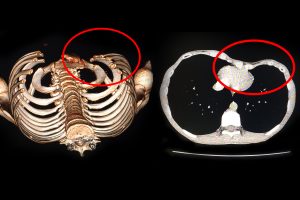

BVXA – ĐIỀU TRỊ NGỰC LÕM BẨM SINH

Ngày 22/02/2017, Bệnh Viện Đa Khoa Xuyên Á (BVXA) đã phẫu thuật chỉnh hình nâng ngực thành công cho em T.V. (16 tuổi, ngụ tại huyện Tân Uyên, tỉnh Bình Dương). Đây là trường hợp lõm ngực bẩm sinh hiếm gặp ở trẻ em. Trước đó 1 ngày, em T.V. được gia đình đưa đến […]